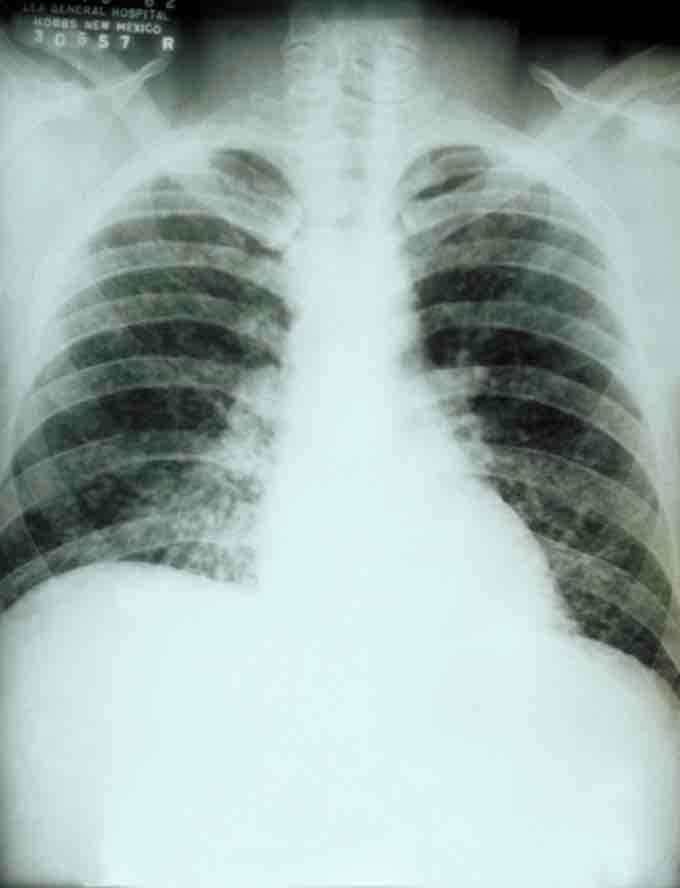

If symptoms of histoplasmosis infection occur, they will start within 3 to 17 days after exposure, with the average being 12 to 14 days. Most affected individuals have clinically silent manifestations and show no apparent ill effects. The acute phase of histoplasmosis is characterized by non-specific respiratory symptoms, often cough or flu-like. Chest X-ray findings are normal in 40 to 70% of cases. Chronic histoplasmosis cases can resemble tuberculosis, and disseminated histoplasmosis affects multiple organ systems and is fatal unless treated.

This is a chest X-ray of a patient with acute pulmonary histoplasmosis.